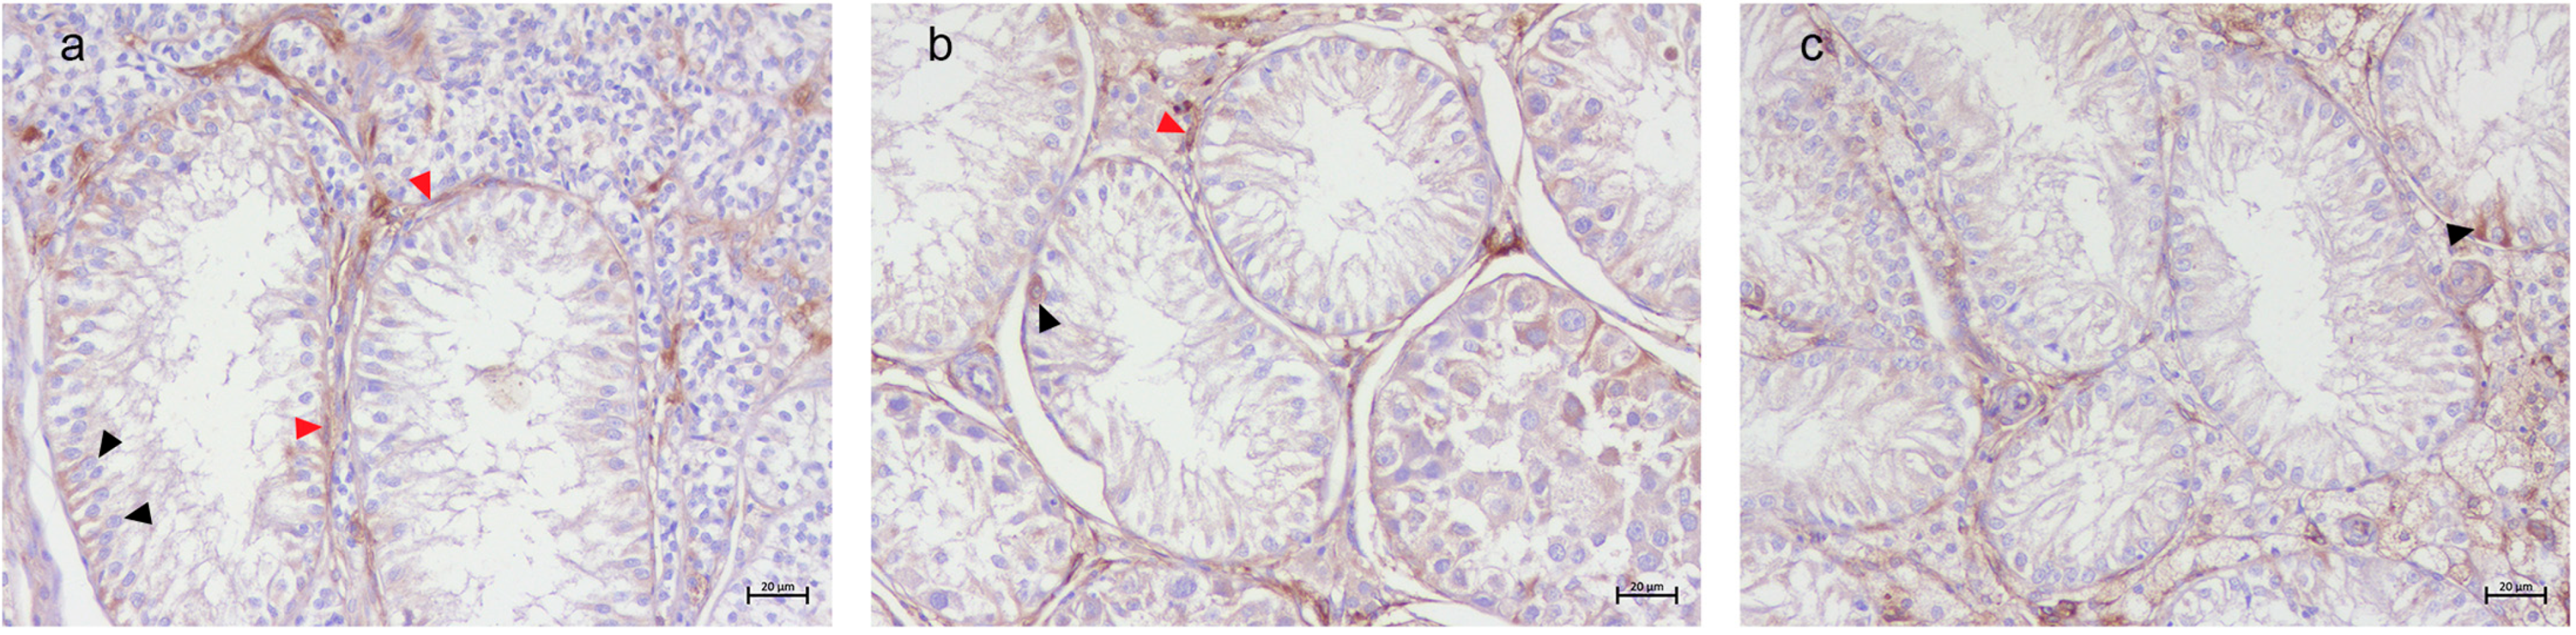

3.2. Immunohistochemical Results